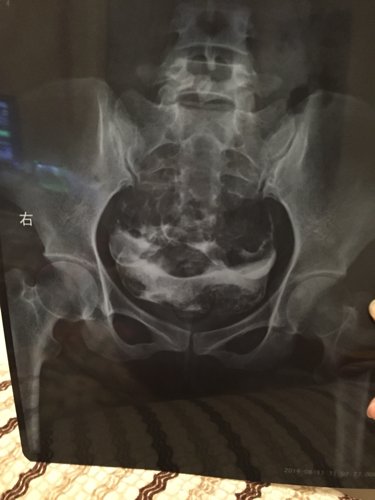

输卵管造影片子有没有问题?严重吗? 点击展开 匿名用户 2014-12-08 22:37 推荐回答 从第一张片子中可以看出右布瓣侧迂曲粘连,看图片不好禁灿行助减诊断。应该有大夫给你看过了。 斛昂杰_tguG 2014-12-09 10:24 宝宝知道提示您:回答为网友贡献,仅供参考。 相关问题 拜托各位请帮我看一下输卵管造影的片子,是个什么情况? 输卵管造影时医生让我坐起穿裤子过15分钟后再拍最后一张片子,这会影响结果的准确性吗? 输卵管碘油造影片子名字和身份证名字不对证明怎么写